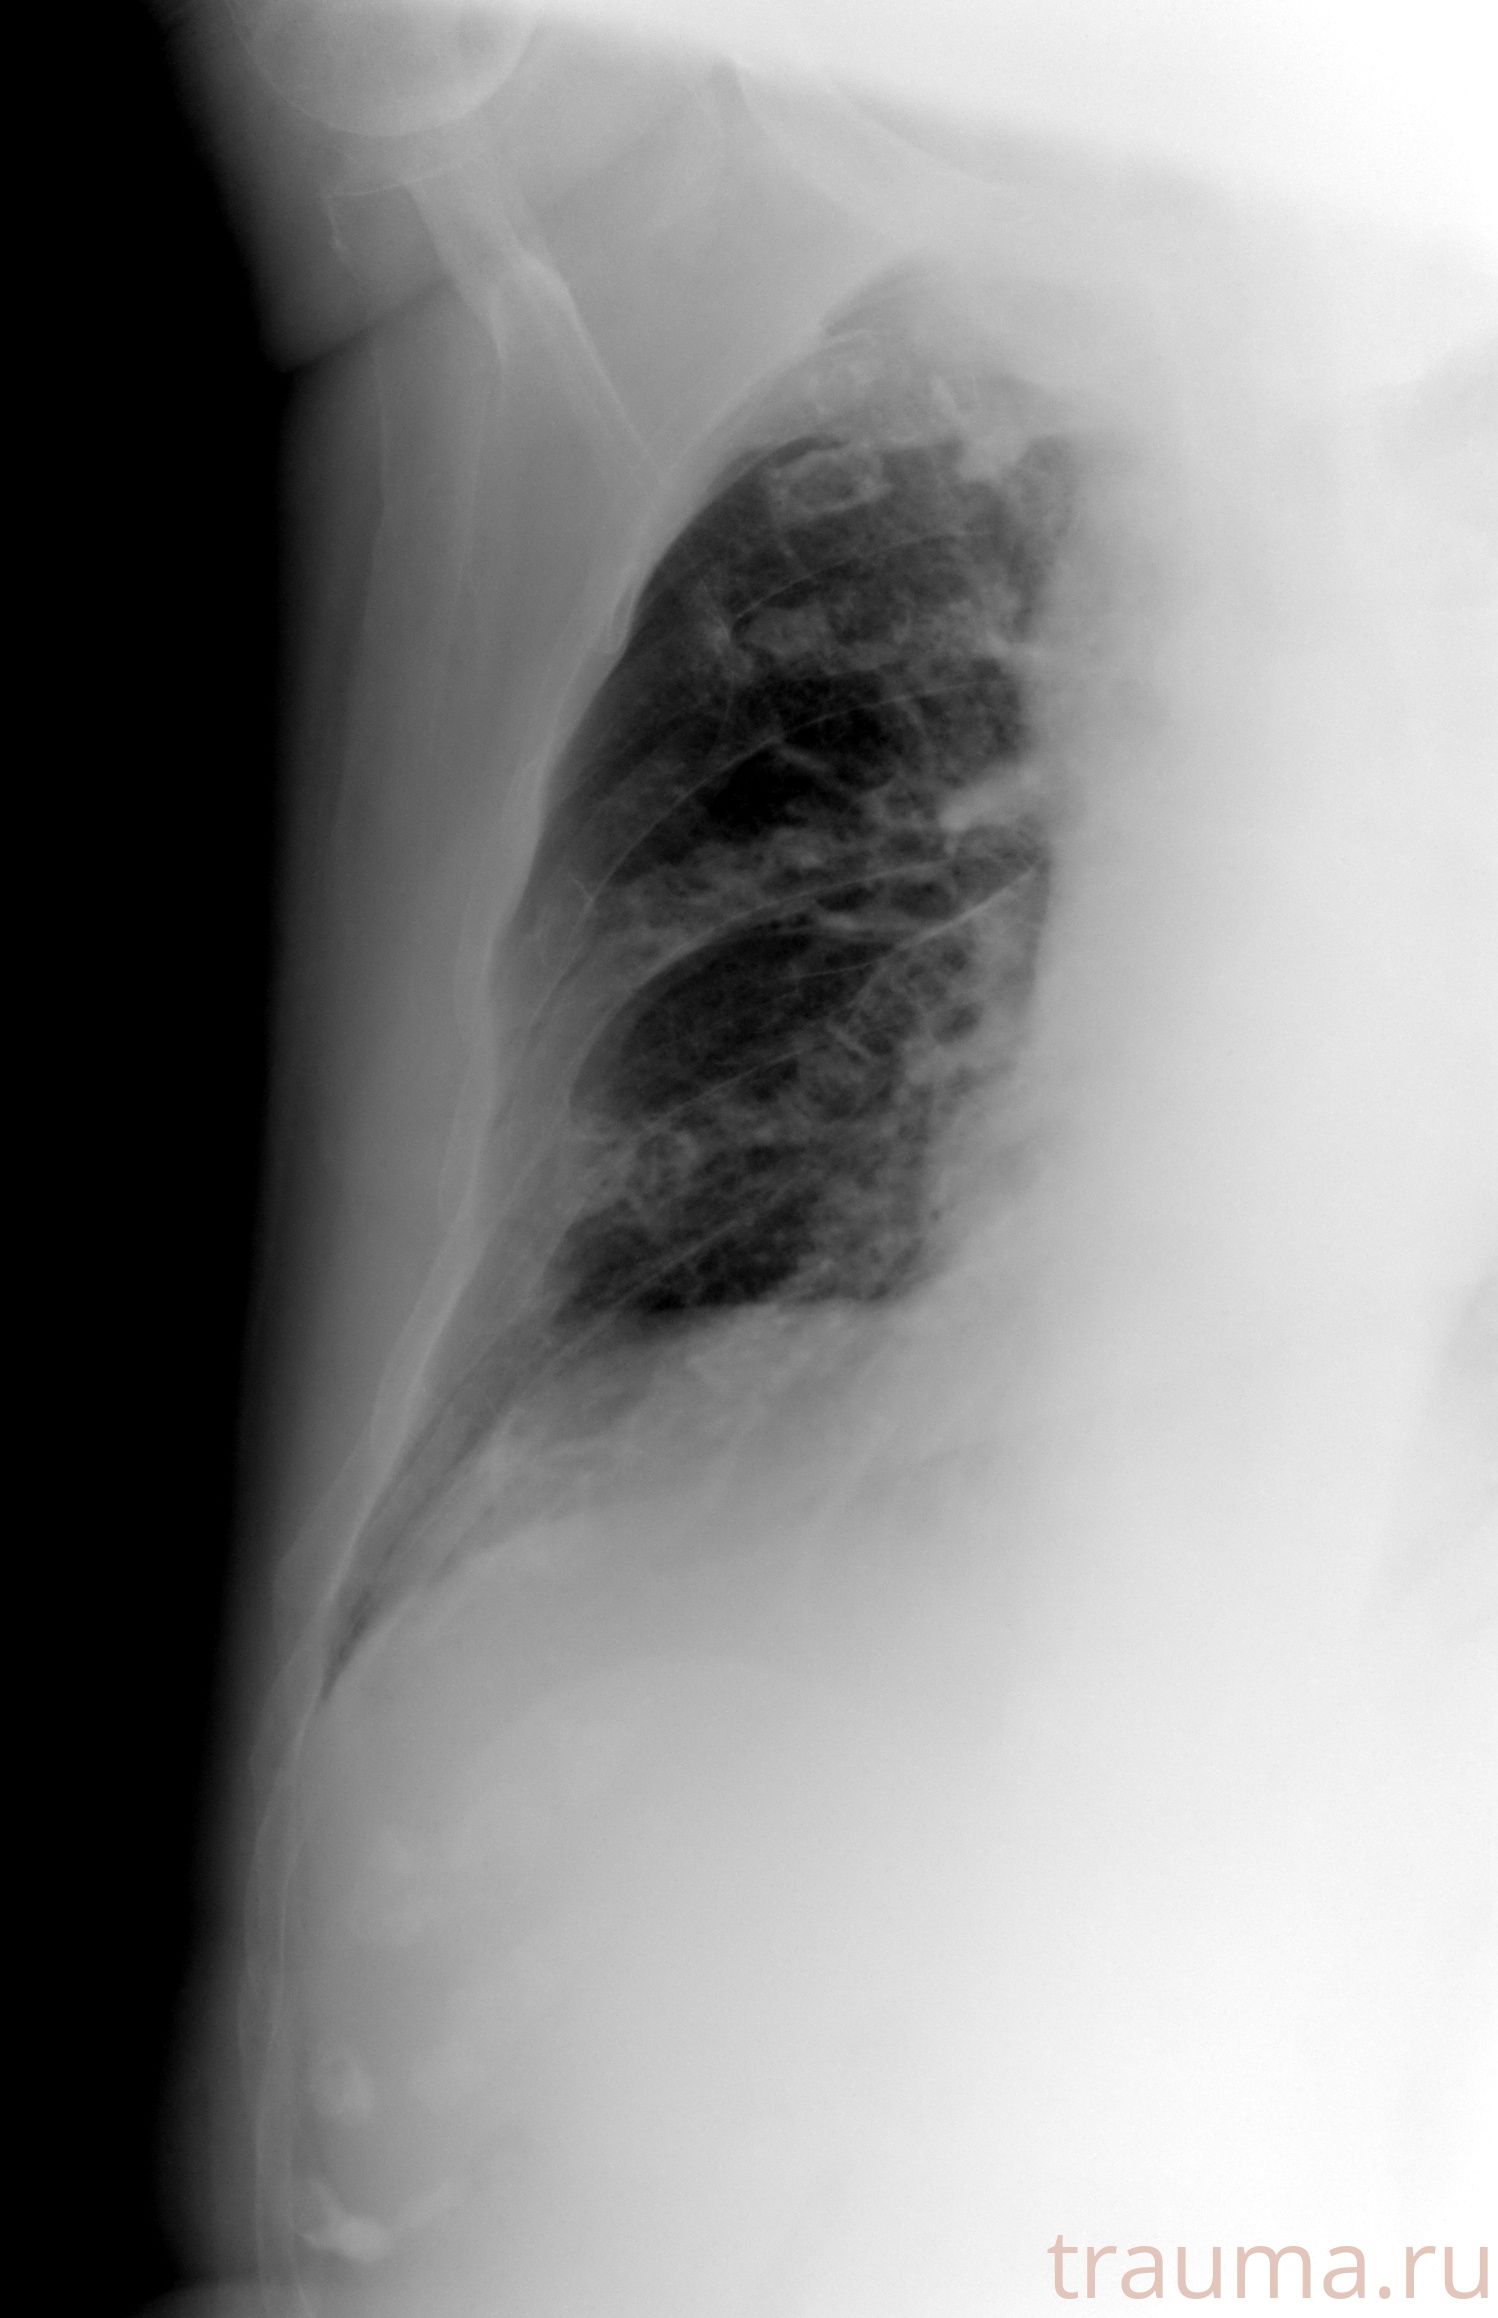

Рентген на дому: по вашему адресу приезжает врач-рентгенолог, травматолог-ортопед с мобильным рентгеновским аппаратом, проводит диагностику травмы или заболевания, делает необходимые рентгенограммы, дает рекомендации по дальнейшему лечению. Получить качественные снимки в домашних условиях возможно благодаря уникальной методике, разработанной МосРентген Центром для института  Склифосовского

при переломе шейки бедра и пневмонии от компании МосРентген Центр - партнера Института имени Склифосовского